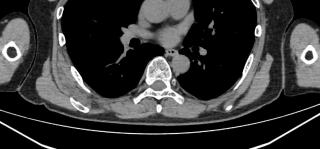

触診、CT、MRI、超音波断層撮影で肩甲骨に接するような腫瘤を認めます。発生する場所や腫瘤の形態から診断します。MRIの所見は筋肉とおなじ吸収域を示し、内部に脂肪が混在します。